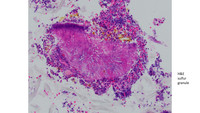

• NRBC

Najmaldin Saki, P...

Nucleated Red Blo...